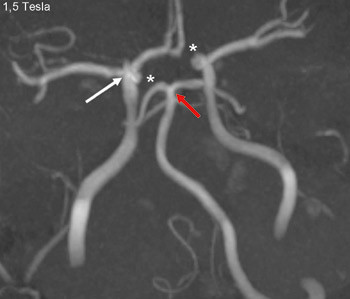

En person i 20-årene med kjent migrene med aura fikk infarkter i høyre arteria cerebri media og begge anteriorgebet (figur 1 viser en magnettomografidiffusjonsvektet serie). Cerebral computer- og magnettomografi med blodstrømsangiografi (MRA) etter innleggelse viste upåfallende strømning uten tegn til disseksjon eller vaskulitt. Hemikraniektomi ble nødvendig etter utvikling av malignt hjerneødem. MR-angiografi i narkose dagen etter operasjonen viste åpne arterier (figur 2 viser en åpen carotistopp (hvit pil), normal basilaristopp (rød pil) samt en ikke-lukket Willis’ sirkel, som er en anatomisk normalvariant (stjerner)). Testing på sentralstimulerende substanser, antikardiolipin, antinukleære antistoffer, nevronantistoffer og tumormarkører ga negative funn. Transøsofageal ekkokardiografi viste et minimalt patent foramen ovale, lite sannsynlig relatert til hendelsen, ifølge kardiolog. Pasienten utviklet alvorlig hjernestammeaffeksjon og MR-angiografi viste forsnevring i arteria basilaris posterior-forgreningen (pilene i figur 3). Arterielle karspasmer ble retrospektivt mistenkt. Den første mistenkte karspasmen i høyre media-/anteriorforgreningen forble udokumentert. Den andre i basilaris-/posteriorforgreningen ble dokumentert postoperativt (pilene i figur 3). Bildene av flere nytilkomne infarkter i bakre kretsløp vises ikke. Tre uker etter hemikraniektomi var ny angiografi normalisert (figur 4).